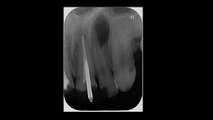

wsr ist die abkürzung für wurzelspitzenresektion. ein chirurgischer eingriff, der in der regel nichts bringt https://www.youtube.com/channel/UCtfezrProo8WbGBSwaEOMIA/search?query=wsr